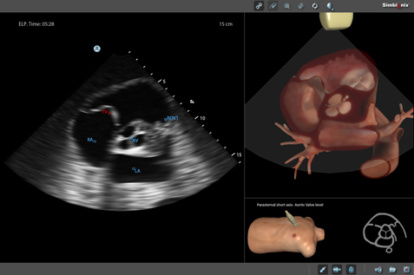

Ultrasound Mentor accelerates the development of basic to advanced technical and cognitive skills, by providing not only the probe manipulation training, but also a didactic environment enabling structured, self-guided learning including step-by-step instructions and educational aids such as 3D anatomical map and probe positioning assistant, all backed up with our progress monitoring tool MentorLearn.

- Advanced diagnostic tools, including Color Doppler, CW, PW, M-mode, and measurements

Bedside Echocardiography Module

Advanced Echo Module

TEE Module

TEE Emergency Module